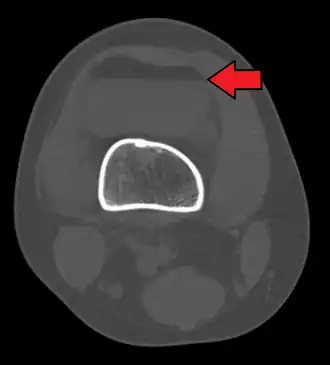

Гемартро́з — кровоизлияние в полость сустава. Гемартроз Характеризуется болью в суставе при сгибе или выпрямлении его.

Возникает при ушибах, чаще при внутрисуставных повреждениях (разрывы капсулы, мениска, вывихи, подвывихи, переломы). Самая частая локализация — коленный сустав.

Кровь заполняет полость сустава и его завороты, вызывая боль, увеличение объёма сустава, ограничение и болезненность движений, отёк, опухлость на месте травмы. Диагноз устанавливается на основании жалоб, объективных данных (клинический осмотр, КТ, УЗИ). Клиническим признаком гемартроза коленного сустава является «симптом флотирующего надколенника» или «симптом льдинки» — когда при надавливании на надколенник он уходит вглубь. Так как гемартроз часто сопровождается повреждением внутрисуставных структур рекомендовано проведение УЗИ, КТ, а по определённым показаниям, МРТ сустава. К числу осложнений относятся переход в хроническое течение с развитием синовита; при инфицировании содержимого сустава может развиться гнойный артрит. Гемартроз опасен выпадением нитей фибрина и развитием спаек в суставе.